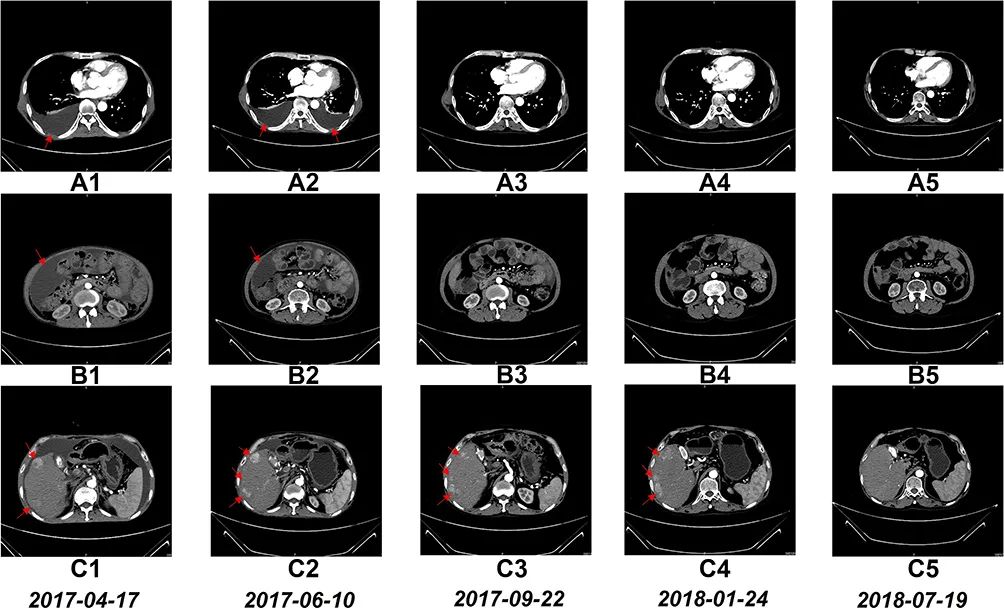

3、影像学变化:CT扫描示,经过6个疗程的NK细胞治疗后,患者的腹水和胸水明显减少;17个疗程后,右肝叶的多个肿瘤尺寸显著缩小。

图3 NK细胞治疗前后的CT扫描结果

图A1~A5:CT扫描示,6个疗程后,患者胸腔积液完全消失;

图B1~B5:CT扫描示,6个疗程后,患者腹水几乎完全消失;

图C1~C5:CT扫描示,17个疗程后,患者肝右叶多个肿瘤尺寸缩小。